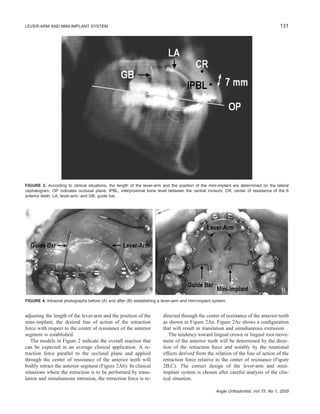

FIGURE 6. For en masse retraction, lever-arm and mini-implant system established in upper arch and 0.018 ϫ 0.018-inch stainless steel

closing-loop mushroom archwire placed in lower arch.

FIGURE 7. Lateral cephalogram taken after establishing a lever-arm and mini-implant system in case 1. The line of action of the retraction

force (LARF) passes through the center of resistance of the 6 anterior teeth (CR) and is parallel to the occlusal plane. In this case, bodily

retraction of the anterior teeth will be expected.

ure 6).

At this point, a progress lateral cephalogram was exposed

to evaluate the anterior tooth movement during retraction.

Cephalometric evaluation revealed that the inclination of

both upper and lower incisors was within normal limits

(Table 1). For the upper arch, the lever-arm and mini-im-

plant system was designed to achieve bodily retraction of

the anterior teeth without anchorage loss (Figure 7), and a

lingual root torque bend was placed in the anterior part of

lower closing-loop mushroom archwire to achieve bodily

retraction of the anterior teeth with some anchorage loss.

During retraction

• intrusive bodily movement of the upper incisors;

• bodily movement of the lower incisors;

• no mesial movement of the upper molars;

• slight mesial movement of the lower molars;

• favorable lingual retrusion of the upper and lower lips.

Cephalometric measurements (Table 1) indicate that during

retraction, the axial inclination and the dental height of the

upper incisors decreased 4.8Њ and 1.8 mm, respectively.